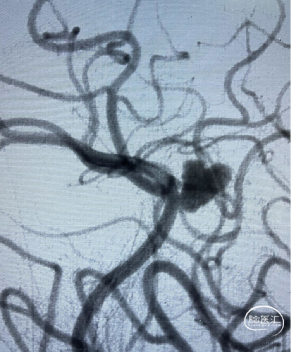

![]() 术前影像

术前影像

DSA:左侧大脑前动脉A2-A3动脉瘤(分叶状)